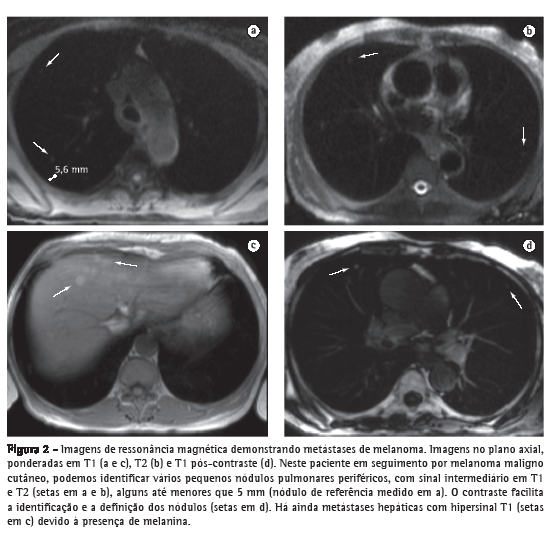

A resolução de contraste tecidual é uma grande vantagem da RM, e o alto

contraste entre o sinal de um nódulo e o parênquima pulmonar normal adjacente pode compensar as demais deficiências do método no estudo dos pulmões. Ainda, a maior sensibilidade da RM ao contraste paramagnético e a alta resolução temporal sem os malefícios da radiação ionizante também permitem uma avaliação da perfusão pulmonar e lesional, o que pode ser útil na caracterização de lesões focais. Dessa maneira, diferentes técnicas podem ser utilizadas não somente na detecção de nódulos pulmonares, mas também na diferenciação entre lesões benignas e malignas.

A RM na detecção de nódulos maiores que 4-5 mm tem acurácia superior à radiografia simples, e possui valores de especificidade e sensibilidade que chegam a 93%, quando comparados aos da TC de multidetectores.(18) A sensibilidade está diretamente relacionada ao tamanho do nódulo, sendo mais baixa para nódulos menores que 5 mm, mas chegando próximo a 100% na detecção de nódulos iguais ou maiores que 10 mm (Figura 2). Dessa maneira, principalmente com as sequências HASTE e GE 3D, a RM pulmonar deve ser utilizada para complementar estudos cardíacos, de lesões mediastinais ou da parede torácica, ou mesmo como uma alternativa à TC na pesquisa de metástases pulmonares. As principais limitações da RM no estudo das lesões focais pulmonares são, principalmente, nos casos de lesões calcificadas e na detecção da linfangite carcinomatosa.(18-20)